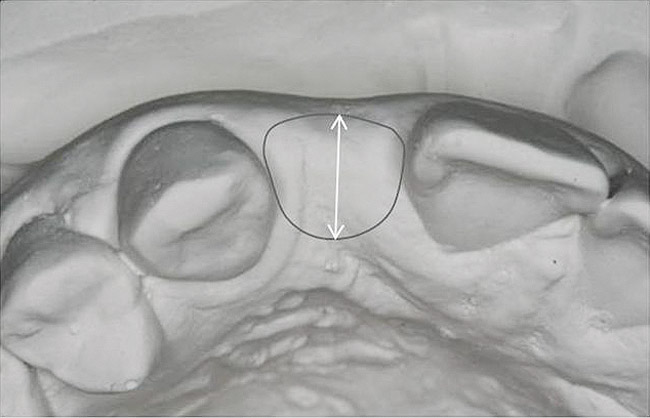

Figure 13   Exploiting study casts for planning single-tooth implant placement and restoration: Mounted study casts permit an estimation of available bone volume (Fig 13); measure the bound edentulous space inter-tooth dimensions (Fig 14); measure the available inter-arch dimension (restorative space) (Fig 15); and evaluate alveolar ridge/tooth relationships (distance from zenith represented by plastic stent to ridge crest) (Fig 16).

Figure 14   Exploiting study casts for planning single-tooth implant placement and restoration: Mounted study casts permit an estimation of available bone volume (Fig 13); measure the bound edentulous space inter-tooth dimensions (Fig 14); measure the available inter-arch dimension (restorative space) (Fig 15); and evaluate alveolar ridge/tooth relationships (distance from zenith represented by plastic stent to ridge crest) (Fig 16).